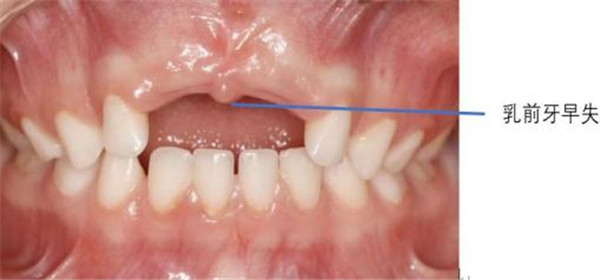

4.乳牙早失诱发错颌畸形

如果牙齿因严重破坏而无法保留被拔除,或者自行脱落过早,旁边的牙齿就会向这个空隙倾斜,导致后继恒牙的萌出空间不足,需要通过矫正来解决这个问题。

3.影响发音和美观

前牙的缺失或损坏会影响孩子发音的清晰度,也可能因牙齿不好看而被同伴取笑,影响自信心和社交。